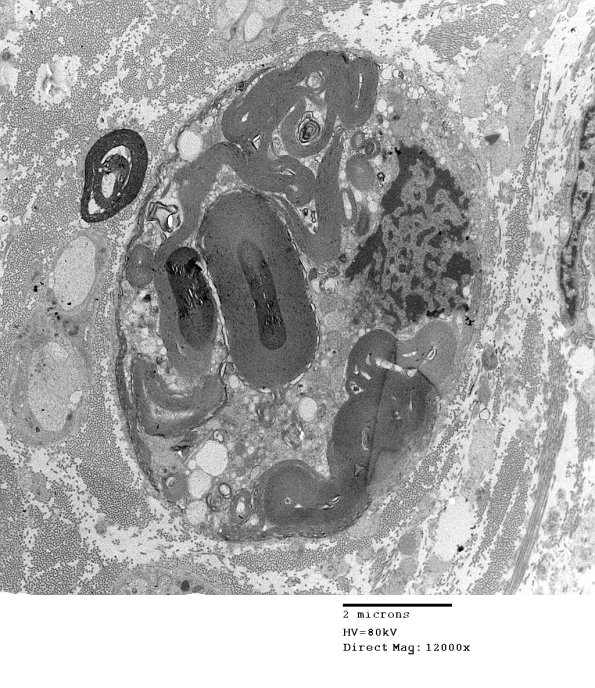

4D3,4 The appearance of this part of the biopsy showed numerous degenerating axons. (electron micrographs)